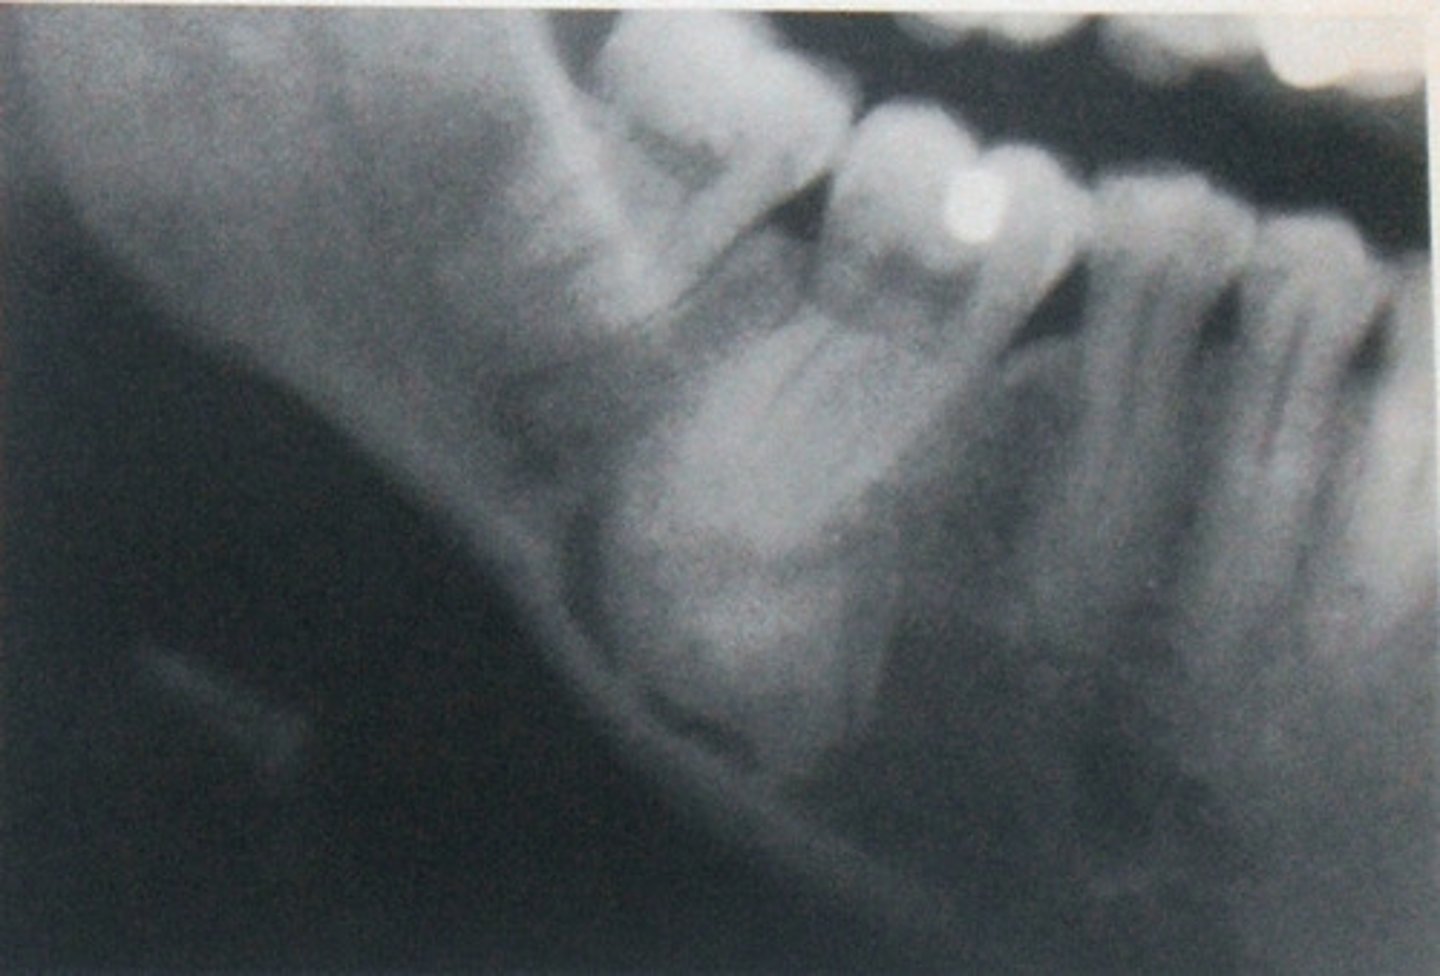

Florid Osseous Dysplasia

widespread form of PCOD.

Normal bone replaced with dense, acellular cemento-ossoeus tissue in background of connective tissue.

poor vascular supply

Clinical Features of Florid Osseous Dysplasia

females

poorly localized

extensive lesions